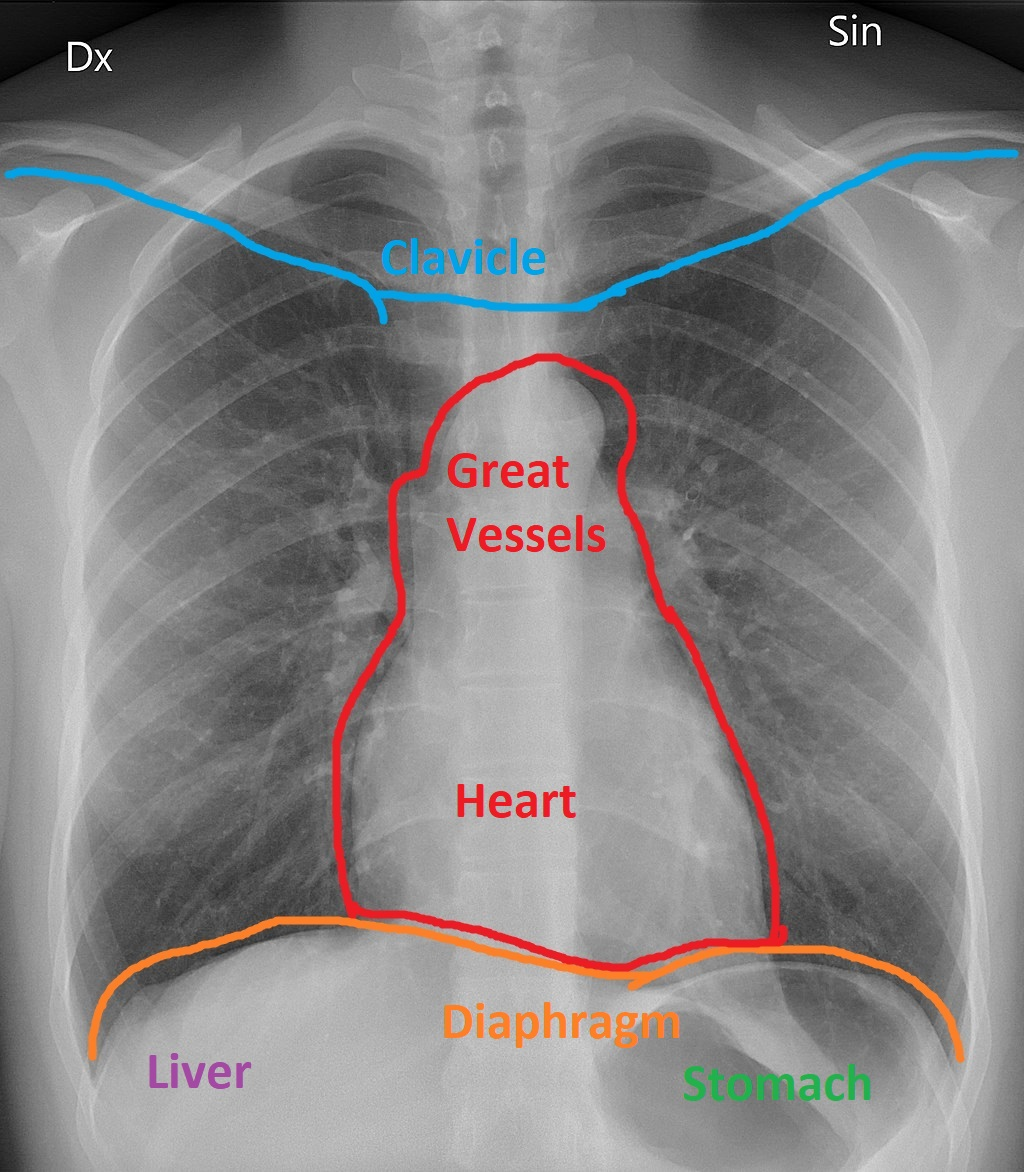

The accompanying image is a chest X-ray with the outline of the heart as it sits in the mediastinum resting atop the diaphragm. Which heart chamber forms the RIGHT border of human hearts?

right atrium